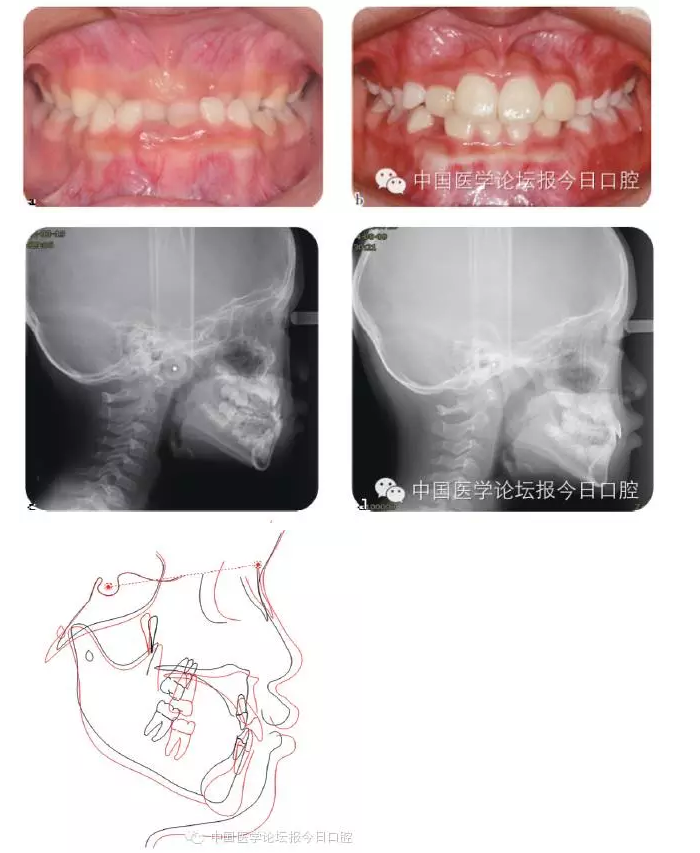

良好的咬合必須是上下頜骨大小位置正常、上下牙大小排列正常,以及上下牙弓的大小與形態(tài)協(xié)調(diào)。臨床功能矯形可調(diào)整上下頜骨大小與位置的不調(diào);臨床正畸治療可矯治牙齒排列異常;而上下牙槽骨大小、形態(tài)不協(xié)調(diào)的早期矯治就是牙槽骨的早期塑形。

牙槽骨的發(fā)育包含牙槽骨長、寬、高三項的發(fā)育,常見的牙槽骨發(fā)育異常是寬度的不足,形成功能性下頜后縮及牙列擁擠。早期的牙槽骨括弓能打開腭中縫,擴大牙弓寬度,增加牙弓周徑,避免功能性Ⅱ類及擁擠的發(fā)生。早期牙槽骨塑形矯治,見圖3。

圖3 上頜牙弓狹窄,對牙槽骨擴弓塑形,促進上下牙弓正常發(fā)育

Ⅲ類骨性畸形的早期矯治

傳統(tǒng)的功能矯形概念認為應在兒童青春發(fā)育高峰前期開始矯治。對于骨性Ⅲ類矯形治療的開始時間,國內(nèi)外一直存在爭議。

華西兒童早期矯治???,總結本科室Ⅲ類骨性矯治的療效,認為Ⅲ類骨性畸形的矯形矯治在第一恒磨牙萌出時(6歲)開始,比在青春發(fā)育高峰前期時(9歲)開始,能得到更多的骨性改變。Ⅲ類骨性畸形的早期功能矯治,見圖4。

圖4 骨性Ⅲ類錯患兒的早期矯治前、后;后續(xù)保持一直持續(xù)至兒童生長發(fā)育結束

必須強調(diào)的是,早期功能矯形治療必須保持到恒牙列初期(12歲),以維持矯形治療的效果,避免由于遺傳因素導致錯牙合畸形復發(fā)。